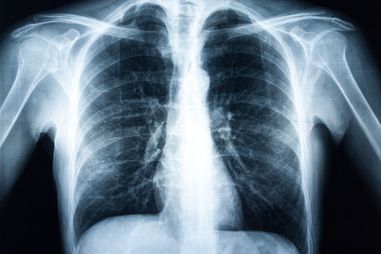

In Austria, approximately 5,000 people a year develop lung cancer and approximately 70% of these are already at an advanced stage at the time of diagnosis. Lung cancer is by far the commonest cause of death from cancer in men and the trend is rising. Due to changes in smoking habits, more women are likely to develop lung cancer in future than has hitherto been the case.